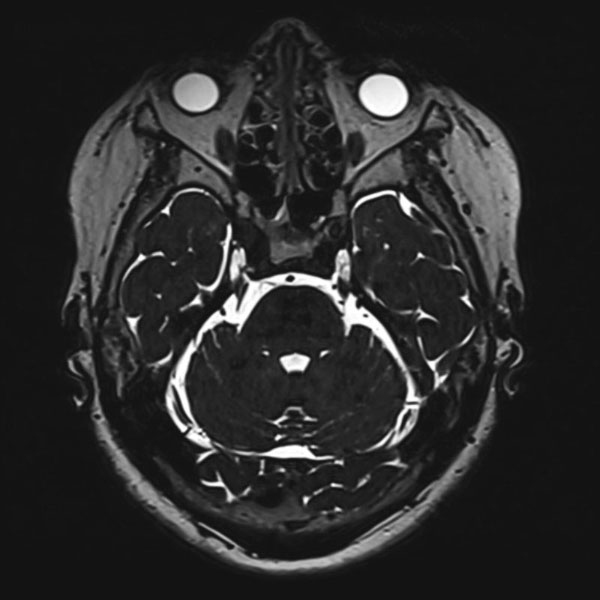

手術前

(MR1)

(CT)